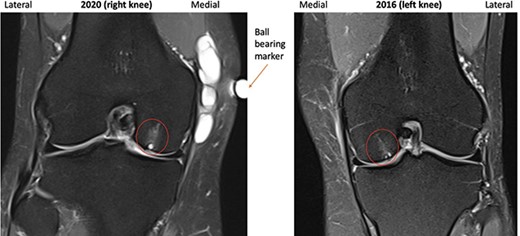

A repeat MRI was performed and reported ‘very similar’ appearances to the left knee, showing a septated ganglion originating from the postero-medial aspect of the joint and subchondral cyst formation with a pattern and location mirroring that which had involved the left knee (Figs 1–3). Reassured by these findings, the patient deferred surgery.

2016 and 2020 T2-weighted MRI in coronal plane with subchondral cyst circled medially.